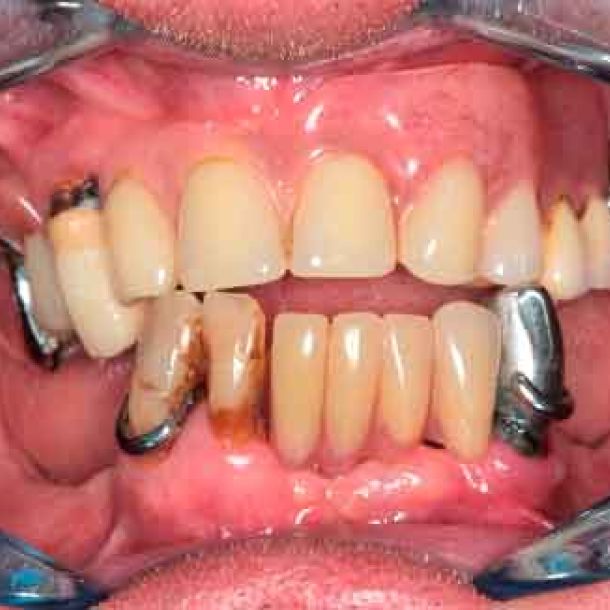

66 years old patient. Wishes to regain functional comfort and improve aesthetics.

Complaints :

- Lack of stability of his removable prosthetics

- Difficulties in eating

- Sagging of the upper lip

The periodontal structures of the remaining teeth are no longer sufficient. An edentulism is considered. The treatment plan is directed towards a removable maxillary complete prosthesis and an implant-supported mandibular complete prosthesis.

Picture - Initial bite situation

3D models - Bite scan from intra-oral scanner